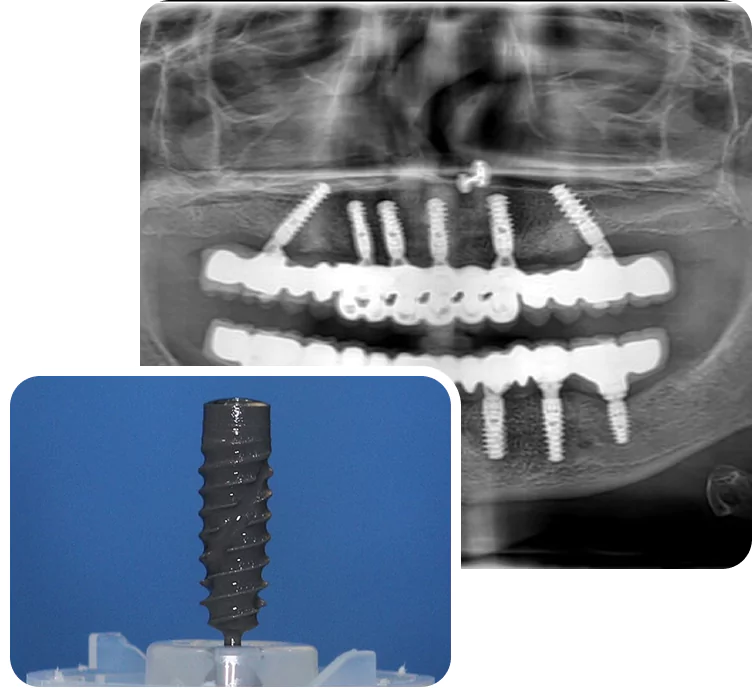

Full Mouth Implants

Get a full arch restored using 4–6 implants for permanent teeth replacement.